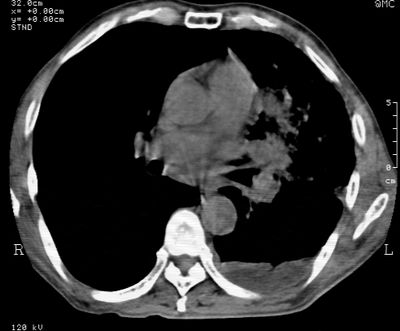

标题: CT24000:M65,胸痛,胸闷月余,既往慢支,肺气肿,肺心病 [打印本页]

标题: CT24000:M65,胸痛,胸闷月余,既往慢支,肺气肿,肺心病

左肺门肿块,相应支气管闭塞,左肺上叶、舌叶大片及散在高密度影,部分呈不张改变,两肺纹粗乱,左侧胸腔积液。考虑左侧中央型肺癌伴阻塞性改变。

左肺门见巨大软组织肿块影,直径约--,境界清,左上肺叶支气管变窄,左上肺舌叶见大片状密实影,余肺纹理增多、紊乱、纤细、部分网格状,两肺透亮度增高,纵隔内见增大多发淋巴结影,心影略左偏,左侧少量胸腔积液。

左侧中央型肺癌伴左上肺舌叶不张、纵隔淋巴结转移,左侧少量胸腔积液。